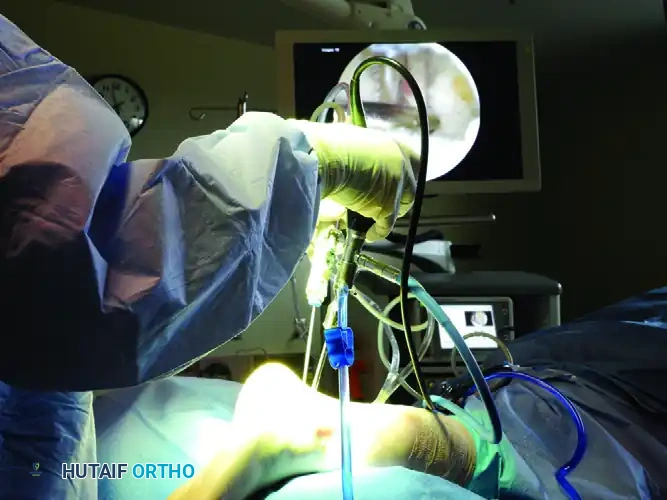

With both portals established, the arthroscope is typically maintained in the posterolateral portal, while working instruments are introduced via the posteromedial portal. The portals can be interchanged as needed for optimal visualization and access.

Introduce a 4.0-mm or 4.5-mm full-radius arthroscopic shaver into the posteromedial portal. Begin by resecting the adipose tissue and the posterior subtalar capsule to clear the visual field.